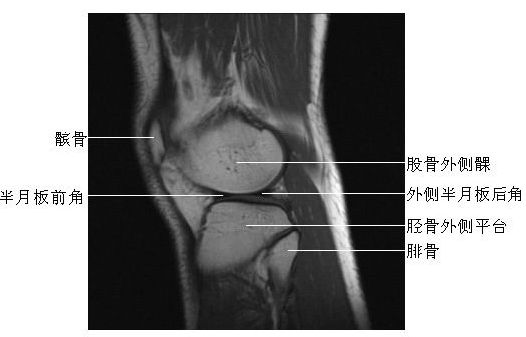

膝关节矢状面-MRI图